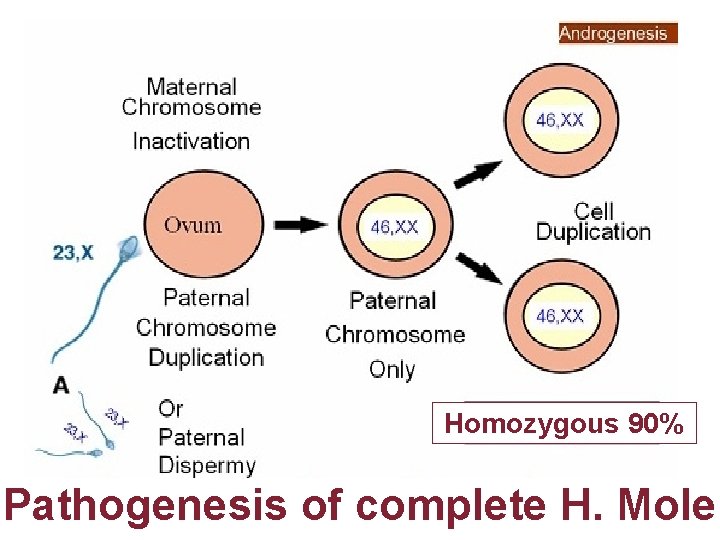

Karyotype

Homozygous 90% Pathogenesis of complete H. Mole